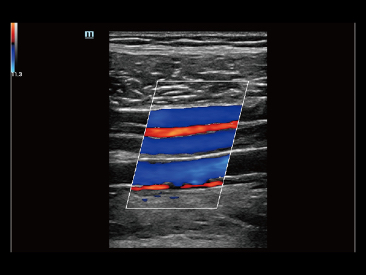

Assim como o n├Łvel de qualidade de imagem premium, o Resona 7 tamb├®m melhora as capacidades de investiga??o cl├Łnica com o revolucion├Īrio Fluxo V para avalia??o hemodin?mica vascular e a aquisi??o de plano mais inteligente do conjunto de dados 3D para diagn├│stico CNS fetal. Combinando a opera??o mais intuitiva baseada em gesto de multi-toques e todos os recursos cl├Łnicos essenciais, Resona 7 est├Ī realmente conduzindo novas ondas na inova??o de ultra-som.